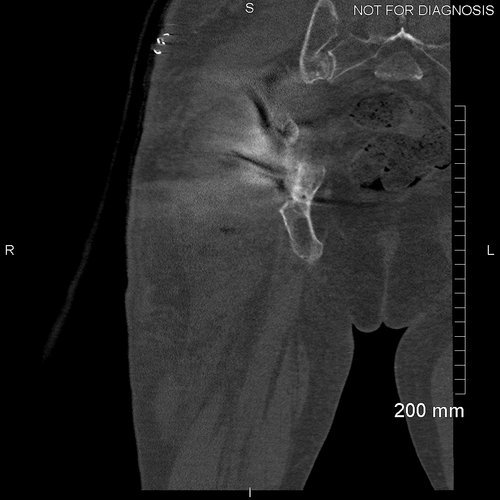

Imaging revealed anterior and medial wall deficiencies with a raised centre of rotation. The posterior column remains intact.

The pre-operative cross sectional imaging demonstrates the extent of the intrapelvic migration